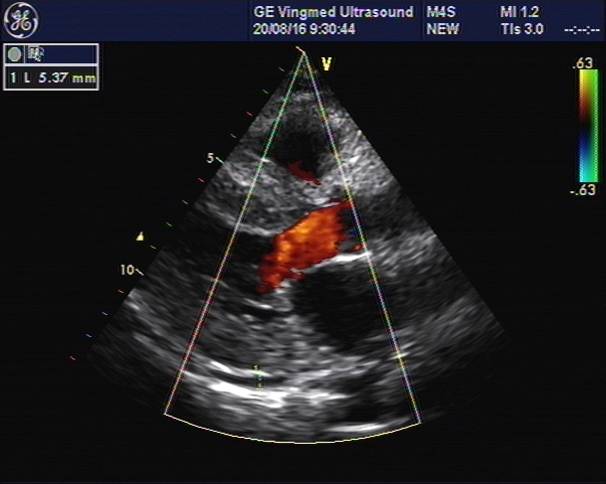

心脏彩超

主动脉根部:30

左室舒张末:40

左室收缩末:26

左房: 34

室间隔: 17

左室后壁: 16

E:79,A:109

EF:64%

E/E’:26